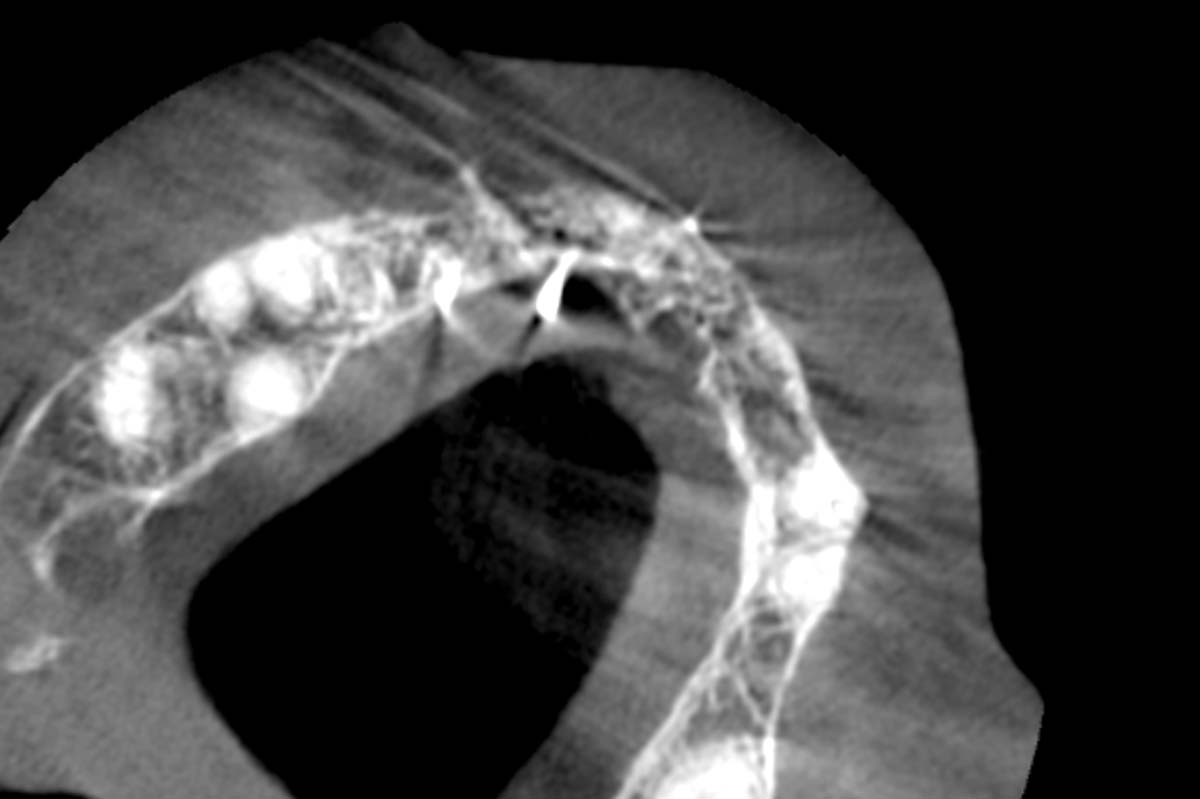

Initial CBCT scan - Fracture of left maxillary incisor and loss of buccal wall